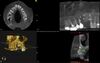

Cas n°3: Mise en Charge Immédiate

Il s’agit d’une intervention Stérile réalisée sous Anesthésie Locale associée à une prémédication sédative, réalisée sur une matinée les mercredi au cabinet. Elle pourra dans certains cas être également réalisée sous Anesthésie Générale au Centre Hospitalier des Vals d’Ardèche. En une seule intervention, nous réalisons les extractions dentaires, pose des implants et leurs aménagements (osseux et/ou tissus mous) ainsi que la mise en place de votre bridge immédiat transitoire en fin d’intervention. Une alimentation molle est indiquée durant les 6 premiers mois avant la réalisation de votre bridge définitif.